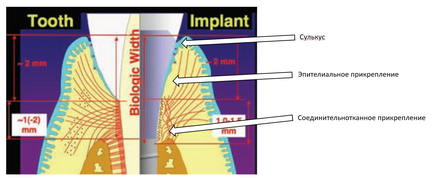

Mielőtt a leírást a második különbség, hogy tisztázni kell egy nagyon fontos pont tekintetében biológiai szélesség (SB).

A „biológiai szélesség” ugyanazt jelenti, mint a fog-fogíny mellékletet. Ahogy közeledik a Apex 3 részből áll:

- Sulkus - sulcus

- epiteliális mellékletet

- kötőszöveti mellékletet

- Kötőszöveti foghoz mutat egy hosszirányú és perpedikulyarno-irányított kollagén rostok. Felhelyezése az implantátum végezzük főleg kollagén rostok párhuzamosan elrendezett az implantátum felületéhez, így eleve kevésbé erősen, mint hogy a fogat.

- Biológiai szélessége mintegy fogászati implantátumok és fogorvosi állandó, és körülbelül egyenlő 3 mm. De bárhol implantátumok ez egy kicsit több, mint 3 mm.